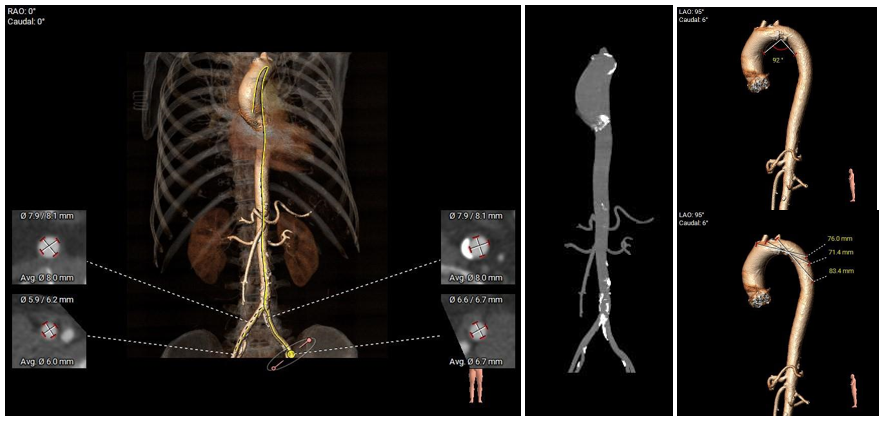

冠脉阻挡风险、横位心及左室大小评估

外周血管入路评估

•主动脉弓、腹主动脉下段、双侧髂总动脉可见散在钙化斑块;所见入路血管直径尚可。

• 瓣环平面与水平夹角为48°,主动脉弓弓距及夹角尚可;